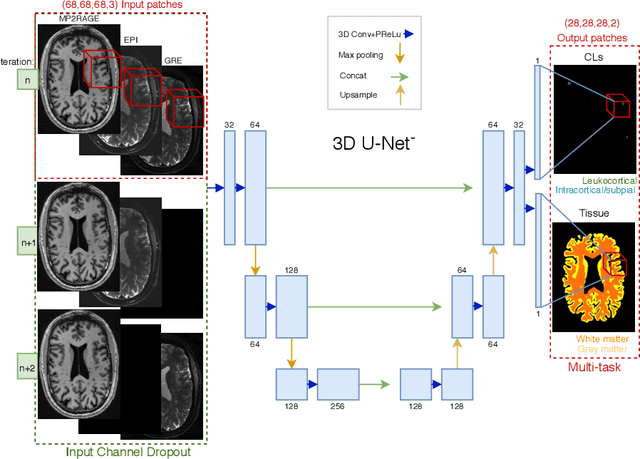

Abstract:The automated detection of cortical lesions (CLs) in patients with multiple sclerosis (MS) is a challenging task that, despite its clinical relevance, has received very little attention. Accurate detection of the small and scarce lesions requires specialized sequences and high or ultra-high field MRI. For supervised training based on multimodal structural MRI at 7T, two experts generated ground truth segmentation masks of 60 patients with 2014 CLs. We implemented a simplified 3D U-Net with three resolution levels (3D U-Net-). By increasing the complexity of the task (adding brain tissue segmentation), while randomly dropping input channels during training, we improved the performance compared to the baseline. Considering a minimum lesion size of 0.75 {\mu}L, we achieved a lesion-wise cortical lesion detection rate of 67% and a false positive rate of 42%. However, 393 (24%) of the lesions reported as false positives were post-hoc confirmed as potential or definite lesions by an expert. This indicates the potential of the proposed method to support experts in the tedious process of CL manual segmentation.